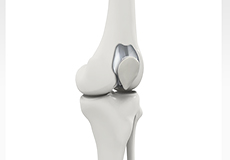

Total Knee Replacement

A Total Knee Replacement (TKR) or Total Knee Arthroplasty is a surgery that replaces an arthritic knee joint with artificial metal or plastic replacement parts called the 'prostheses'.